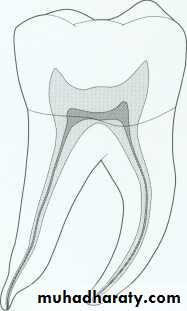

Maxillary first molar.

* Fourth canal (55-74% of teeth) located in the mesiobuccal root.Canal configuration is usually type II or type IV in mesiobuccal root

* The palatal and distobuccal roots usually present a type I configuration.* The length of this tooth is 22mm*Apical-buccal curvature of the palatal root.

* The palatal root slightly longer than the buccal roots.* The pulp chamber is quadrilateral in shape and wider buccopalatally than mesiodistally.* it has four pulp horns, the mesiobuccal is the longest and sharpest in outline.

* The distobuccal pulp horn is smaller than the mesiobuccal but larger than the two palatal pulp horns.* the floor of the pulp chamber is just apical to the cervix, rounded and convex towards the occlusal.

*the minor mesiobuccal canal if present lies on a line joining the main mesiobuccal and palatal canal orifices.*the distobuccal root is closer to the middle of the tooth than to the distal wall.

* The distobuccal canal is the shortest and finest of the three canals.* the palatal canal is the largest and longest of three canals and in 50% the canal curved buccally in apical third.